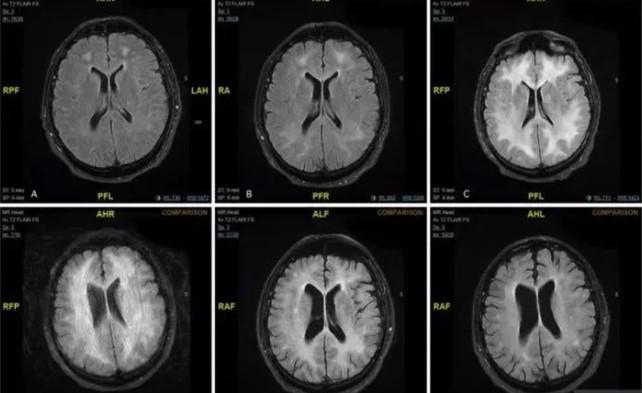

De acuerdo con el doctor Damín, el consumo de cocaína puede producir alteraciones en todo el organismo humano. “En el momento en que se consume la cocaína se producen alteraciones a nivel cardíaco y cerebral. A nivel cardíaco, altera las propiedades del corazón. Aumenta la frecuencia cardíaca, la presión arterial y se puede generar arritmias. A nivel cerebral, se produce una hiperexcitación que puede desencadenar convulsiones o con un cuadro de agitación o delirio”, dijo el profesional que es coautor del libro Toxicología.

Además, el consumo de cocaína puede generar un ataque cerebrovascular y hemiplejias y provocar fiebre exagerada que pone en riesgo la vida. “Puede causar infartos en el intestino o el riñón y alucinaciones. También puede producir afección de acuerdo con vía de ingreso. No es lo mismo si la cocaína se recibe por vía nasal (puede producir perforación del tabique) o por inyección (puede afectar las venas)”, afirmó Damín.